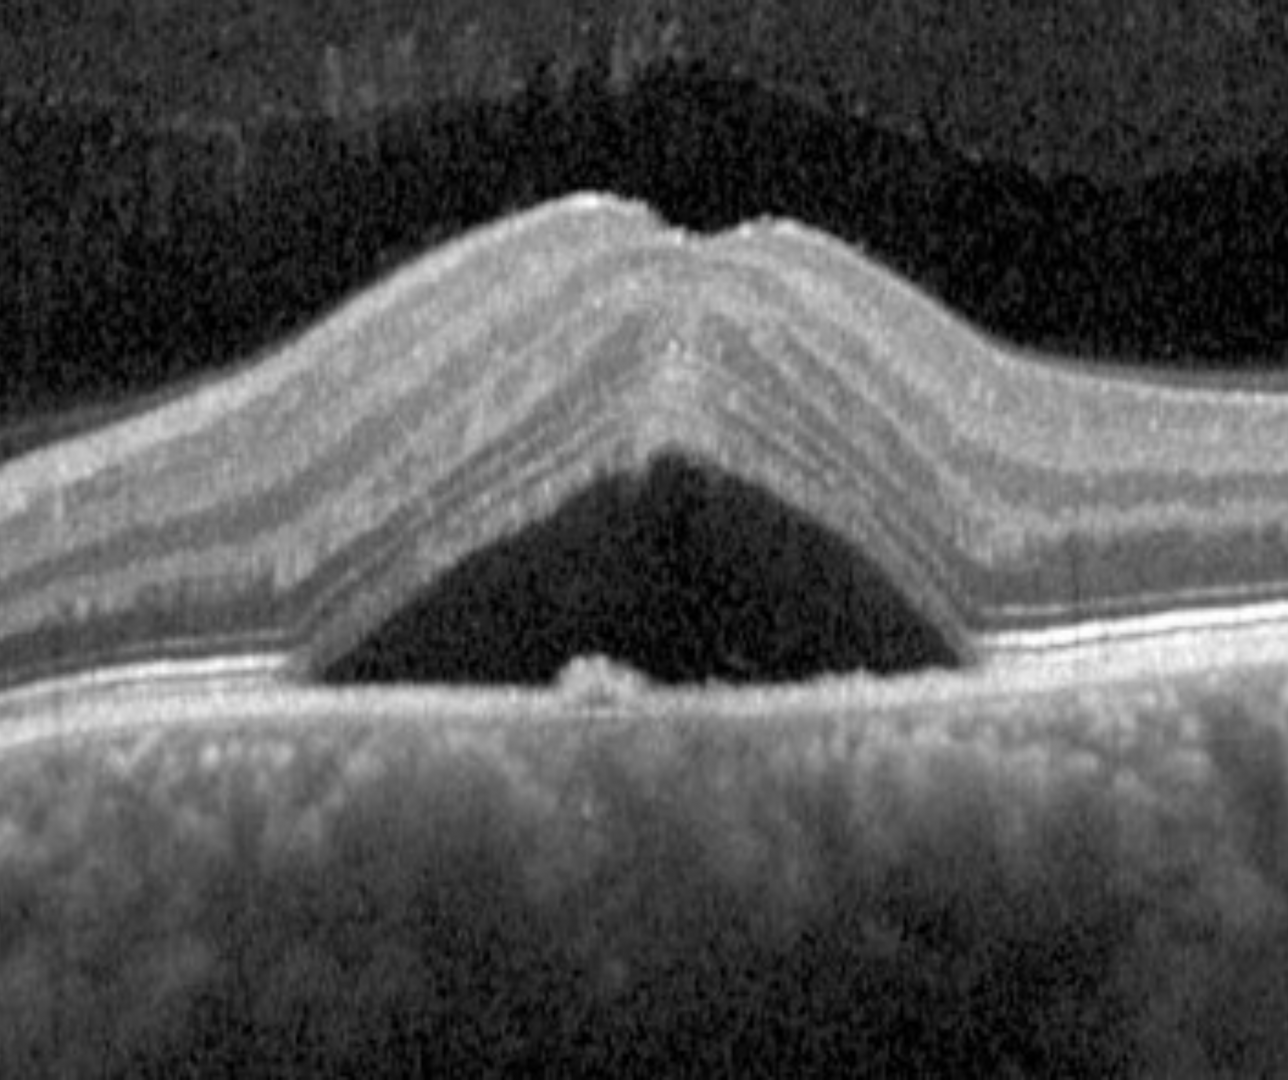

Exudative retinal detachment is characterised by the accumulation of subretinal fluid in the absence of a retinal break or retinal traction. It occurs from a breakdown of the inner or outer blood-retinal barrier.

Dome-shaped maculopathy